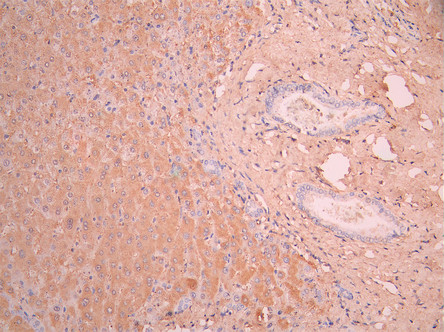

IHC image of CSB-RA001939MA1HU diluted at 1:50 and staining in paraffin-embedded human liver tissue performed on a Leica BondTM system. After dewaxing and hydration, antigen retrieval was mediated by high pressure in a citrate buffer (pH 6.0). Section was blocked with 10% normal goat serum 30min at RT. Then primary antibody (1% BSA) was incubated at 4°C overnight. The primary is detected by a Anti-Human lgG, Fcy Fragment Specific labeled by HRP and visualized using 0.05% DAB.